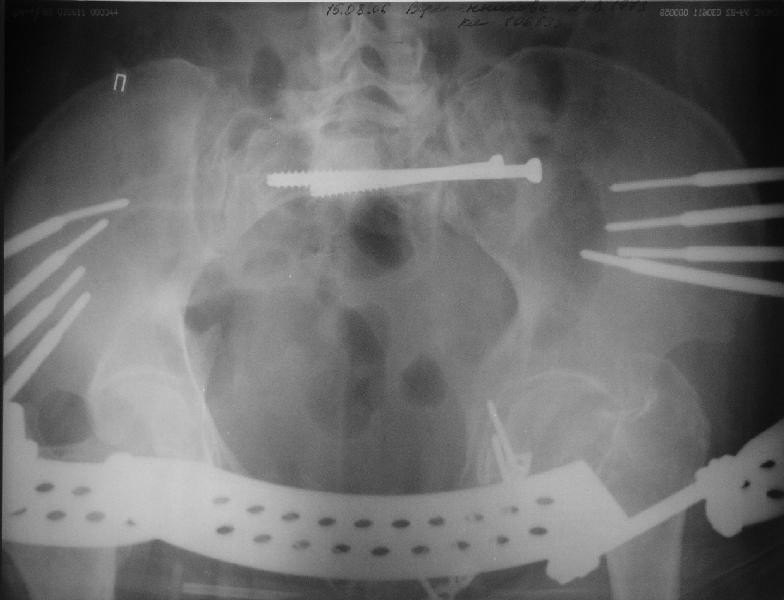

Прооперировали молодую девушку 32 лет спустя 9 мес после травмы.

Имелся стойкий болевой синдром, неопороспособность левой н/конечности, моторные и сенсорные нарушения в левой голени и стопе, патологическая подвижность левой половины таза. Первым этапом закрыто в аппарате исправили деформацию ( в течении 2,5 нед). Вторым закрытое введение илиосакральных винтов в крестец (канюллированные 7,2 мм Chm) + туннелизация зоны псевдоартроза спицама Киршнера, реконструкция передних отделов таза, накостный остеосинтез . Аппарат частично демонтирпован, оставлена "передняя рама" После устранения деформации отмечен регресс неврологической симптоматики, уменьшение болевого синдрома. Интересующие вопросы: 1. Прогноз для сращения псевдоартроза крестца. 2. сроки нагрузки весом левой половины таза. Буду очень признателен за ваши мнения по этому поводу.A female 32 y.o. admitted to our unit 9 months after initial injury with pain, inability to bear weight at the left lower limb, sensor and motor disturbances in the left foot and tibia, with mobility of the left hemipelvis.At first closed reduction was performed by an external fixator within 2,5 weeks. After correction her pain decreased and some neurological progress was achieved. Now two iliosacral screws 7,2 mm were inserted, and anterior lesion was fixed by a plate. External fixator was partially unmounted, only anterior frame left in place.Images attached.How would you evaluate chances of healing of the sacrum with the current position?When would you allow weight-bearing of the left leg?THX in advance.